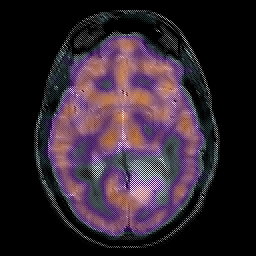

Glioma overlay -- Slice #13

[Home][Help][Clinical] Slice 13